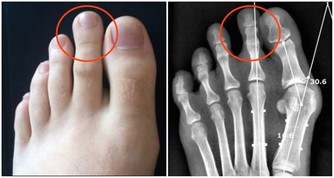

3、睡前泡腳

天熱也要堅持臨睡前用熱水泡腳,這樣有利於促進體內血液循環,刺激腳底穴位和經絡,幫助睡眠,一個良好的睡眠也是起到補充陽氣的作用的。